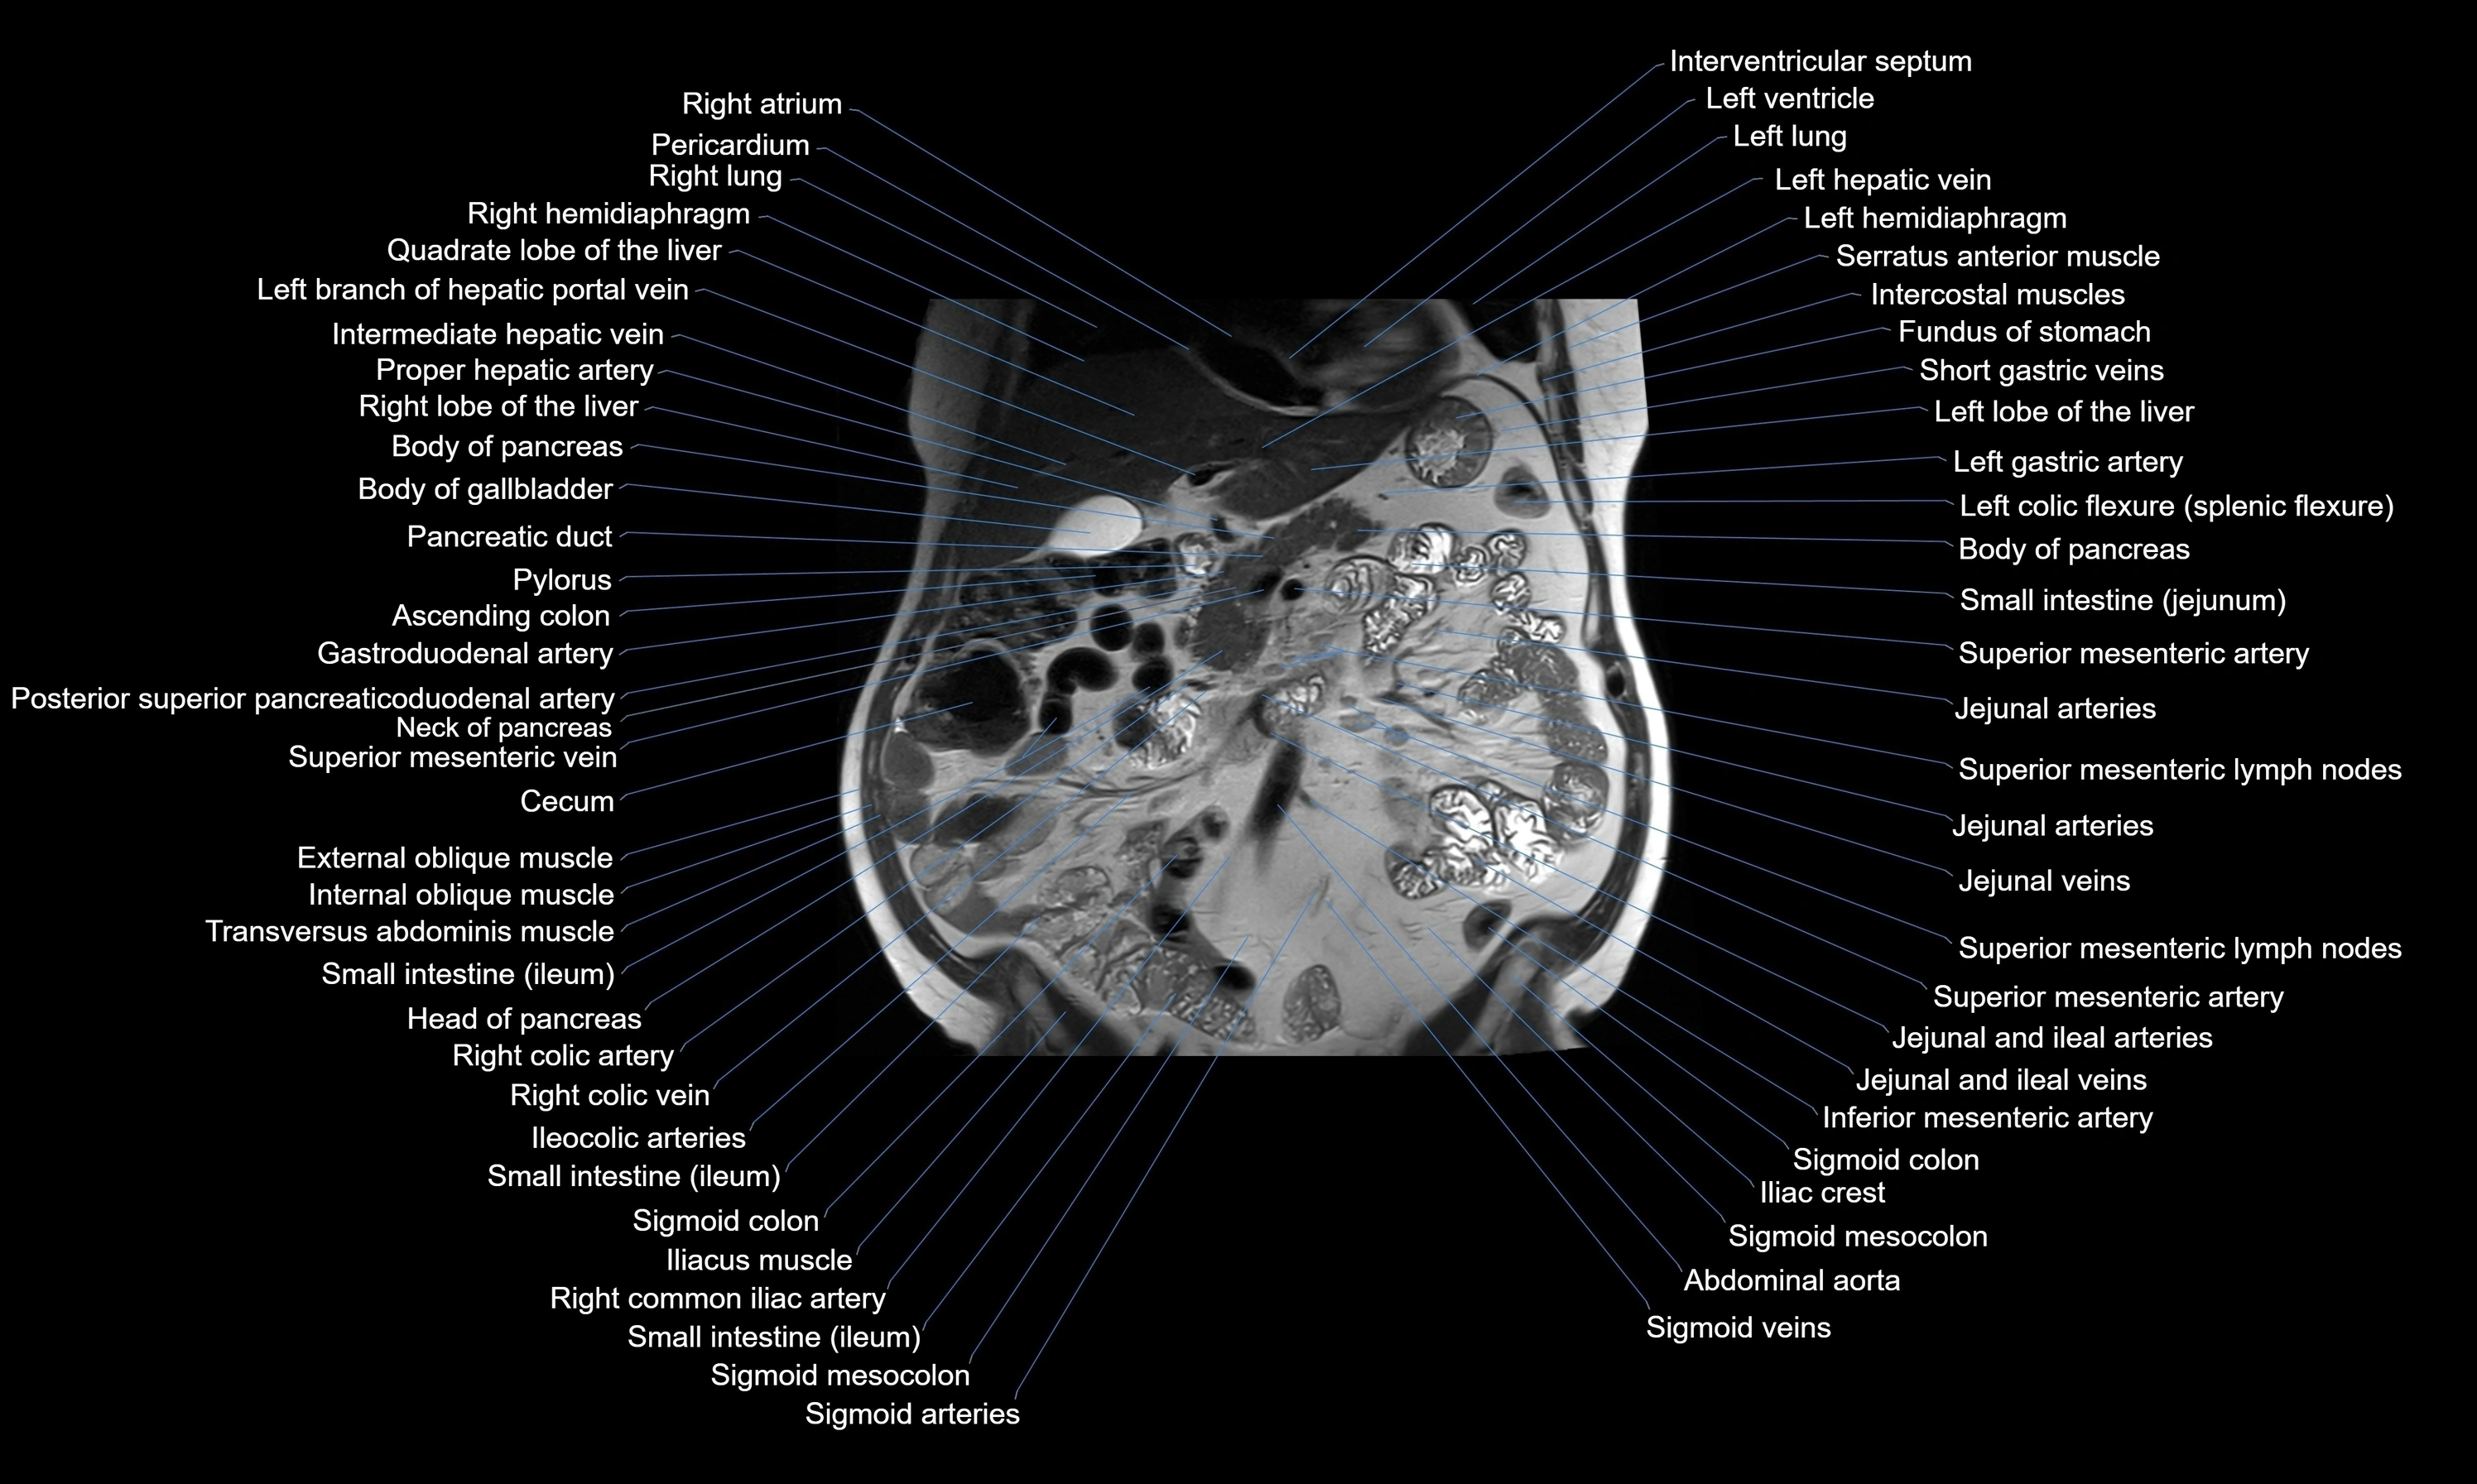

MRI images